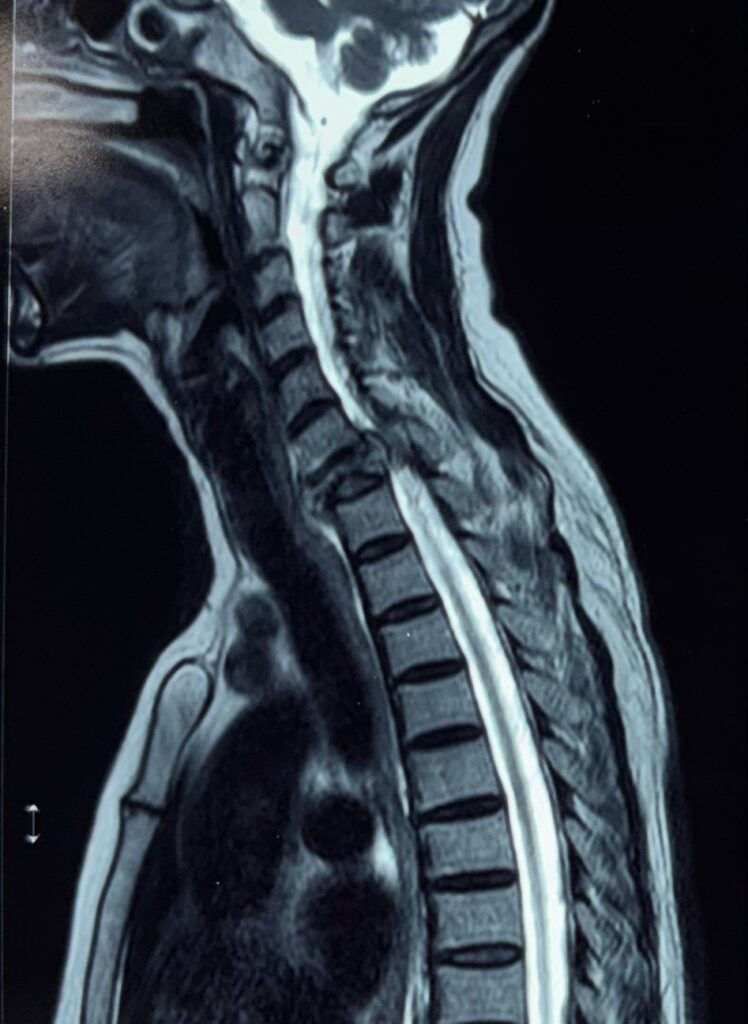

• MRI scan: The most important test to detect spinal cord tumors clearly

These tests help determine the tumor’s size, type, and exact location.

Cases treated by Spine Specialist Dr. Gaurav Sandeep Gupta